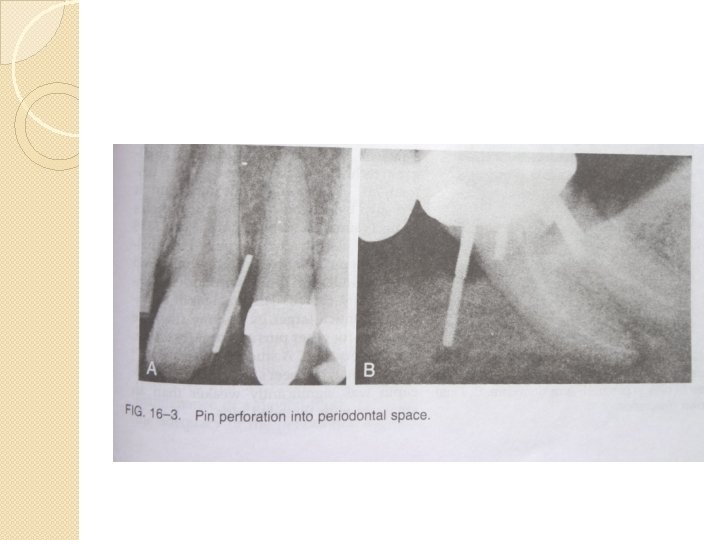

COMPLICATIONS Drill breakage Pin breakage Loose pins Heat generation Dentinal cracks Perforation into pulpal space or external tooth surface